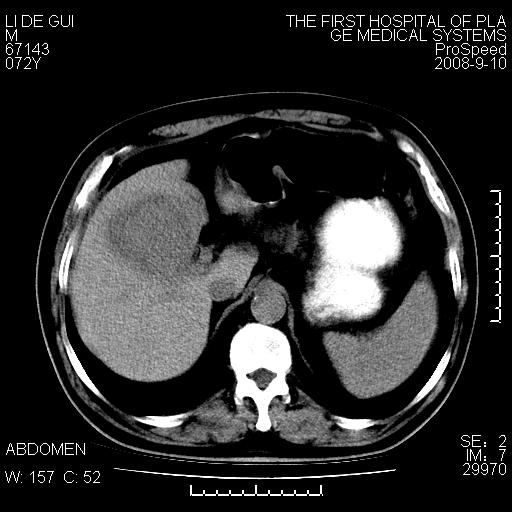

标题: CT17988:腹部肿块两年,肿块大小无变化,患者无不适,自我 [打印本页]

标题: CT17988:腹部肿块两年,肿块大小无变化,患者无不适,自我

胆囊占位性病变(黄色肉芽肿性胆囊炎?)。

考虑-----胆囊血肿机化或胆囊癌或腺肌增生症------增强

胆囊占位性病变,增强。